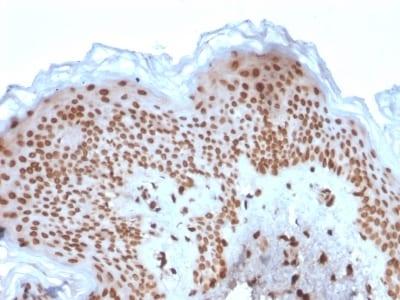

Positive Control

K-562, HeLa or Jurkat cells. Kidney or Skin

Nuclear membrane

Antibody application notes

Higher concentration may be required for direct detection using primary antibody conjugates than for indirect detection with secondary antibody|Immunohistology (formalin): 1-2 ug/mL for 30 minutes at RT|Staining of formalin-fixed tissues requires boiling tissue sections in 10 mM citrate buffer, pH 6.0, for 10-20 minutes followed by cooling at RT for 20 minutes|Optimal dilution for a specific application should be determined by user